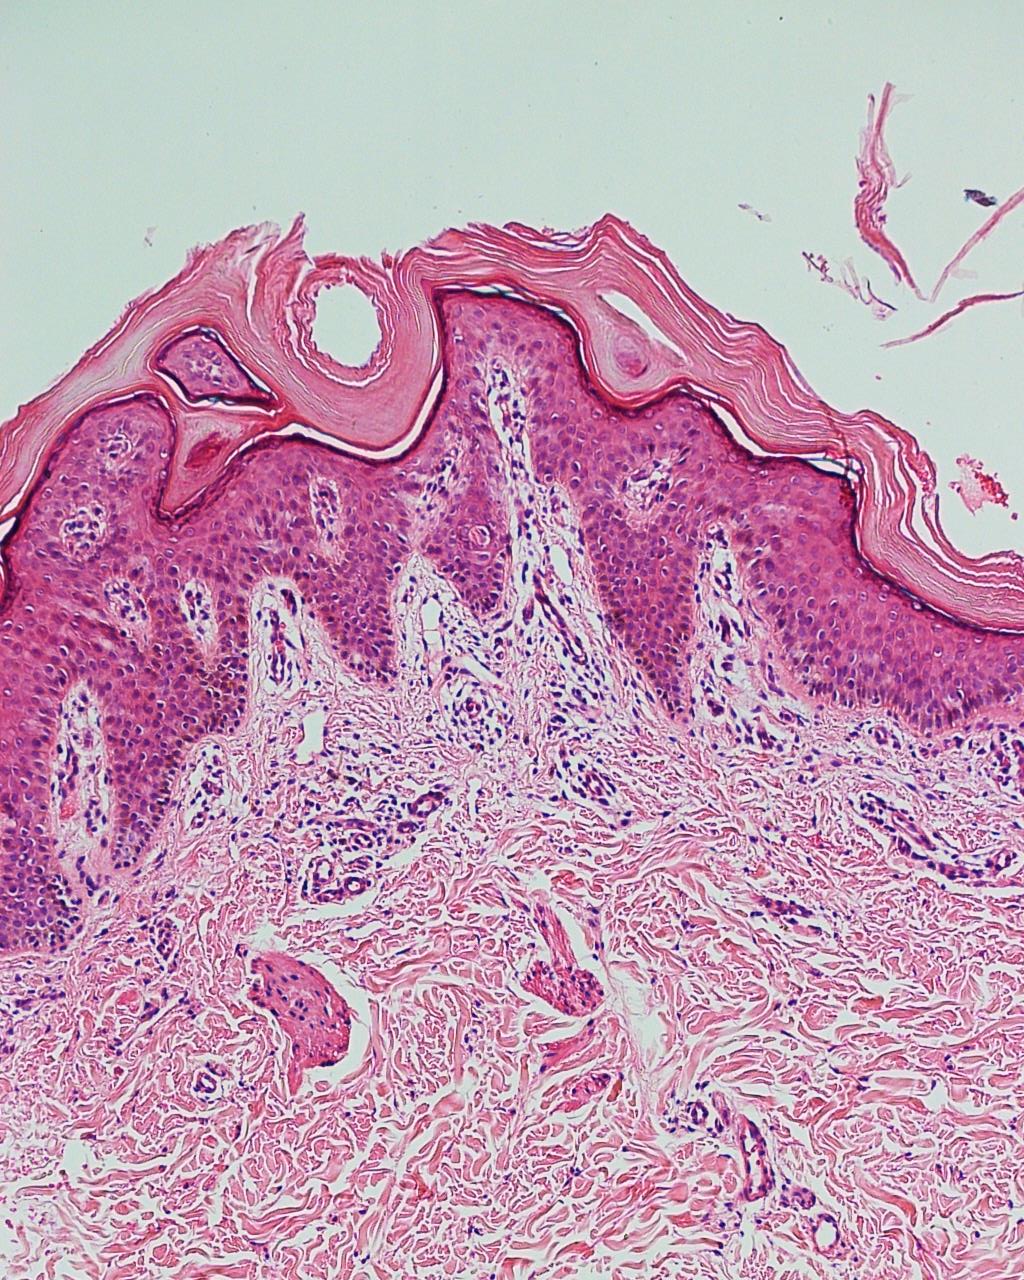

A ictiose lamelar congênita é uma genodermatose autossômica recessiva rara, de expressividade variável e envolve uma mutação no gene TGM1 no cromossomo 14, além de outros. Aparente ao nascimento, o neonato geralmente está envolvido por colódio. As taxas de renovação epidérmica podem diferenciar os tipos de ictiose, caracterizando-as em transtornos da hiperproliferação epidérmica ou de retenção prolongada da camada córnea. O acomentimento cutâneo necessita de atenção diferenciada, pois os casos variam quanto à severidade. Os autores deste artigo descrevem um caso dessa rara anormalidade.